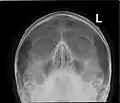

CT scans, radiographs (x-ray) and other illustrations